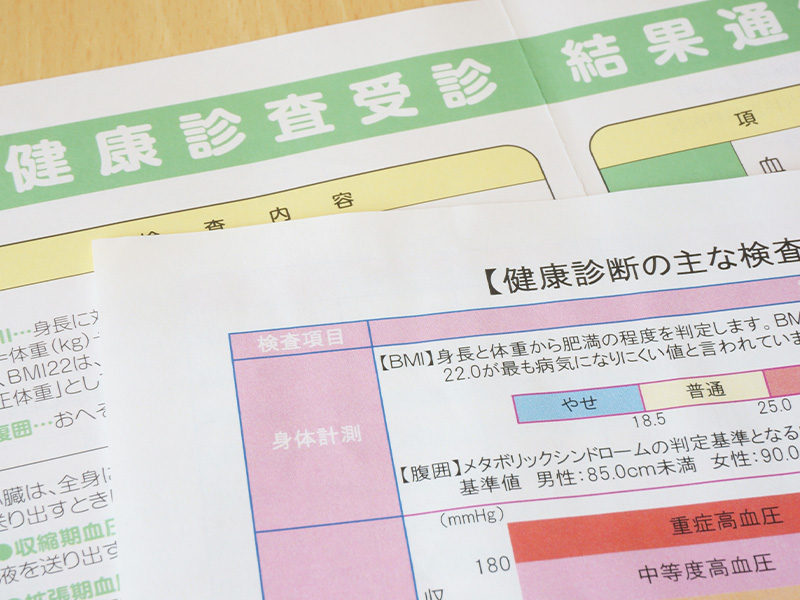

各種がん検診CANCER SCREENING

特定健診と特定保健指導(動機付け支援・積極的支援)を実施

事業所健診

事業所の定期健康診断を行います。事業主様には労働基準監督署報告用(様式第6号)の集計表、結果一覧、有所見者一覧等の帳票を、受診者様にはコメントつきの結果報告書を発行します。